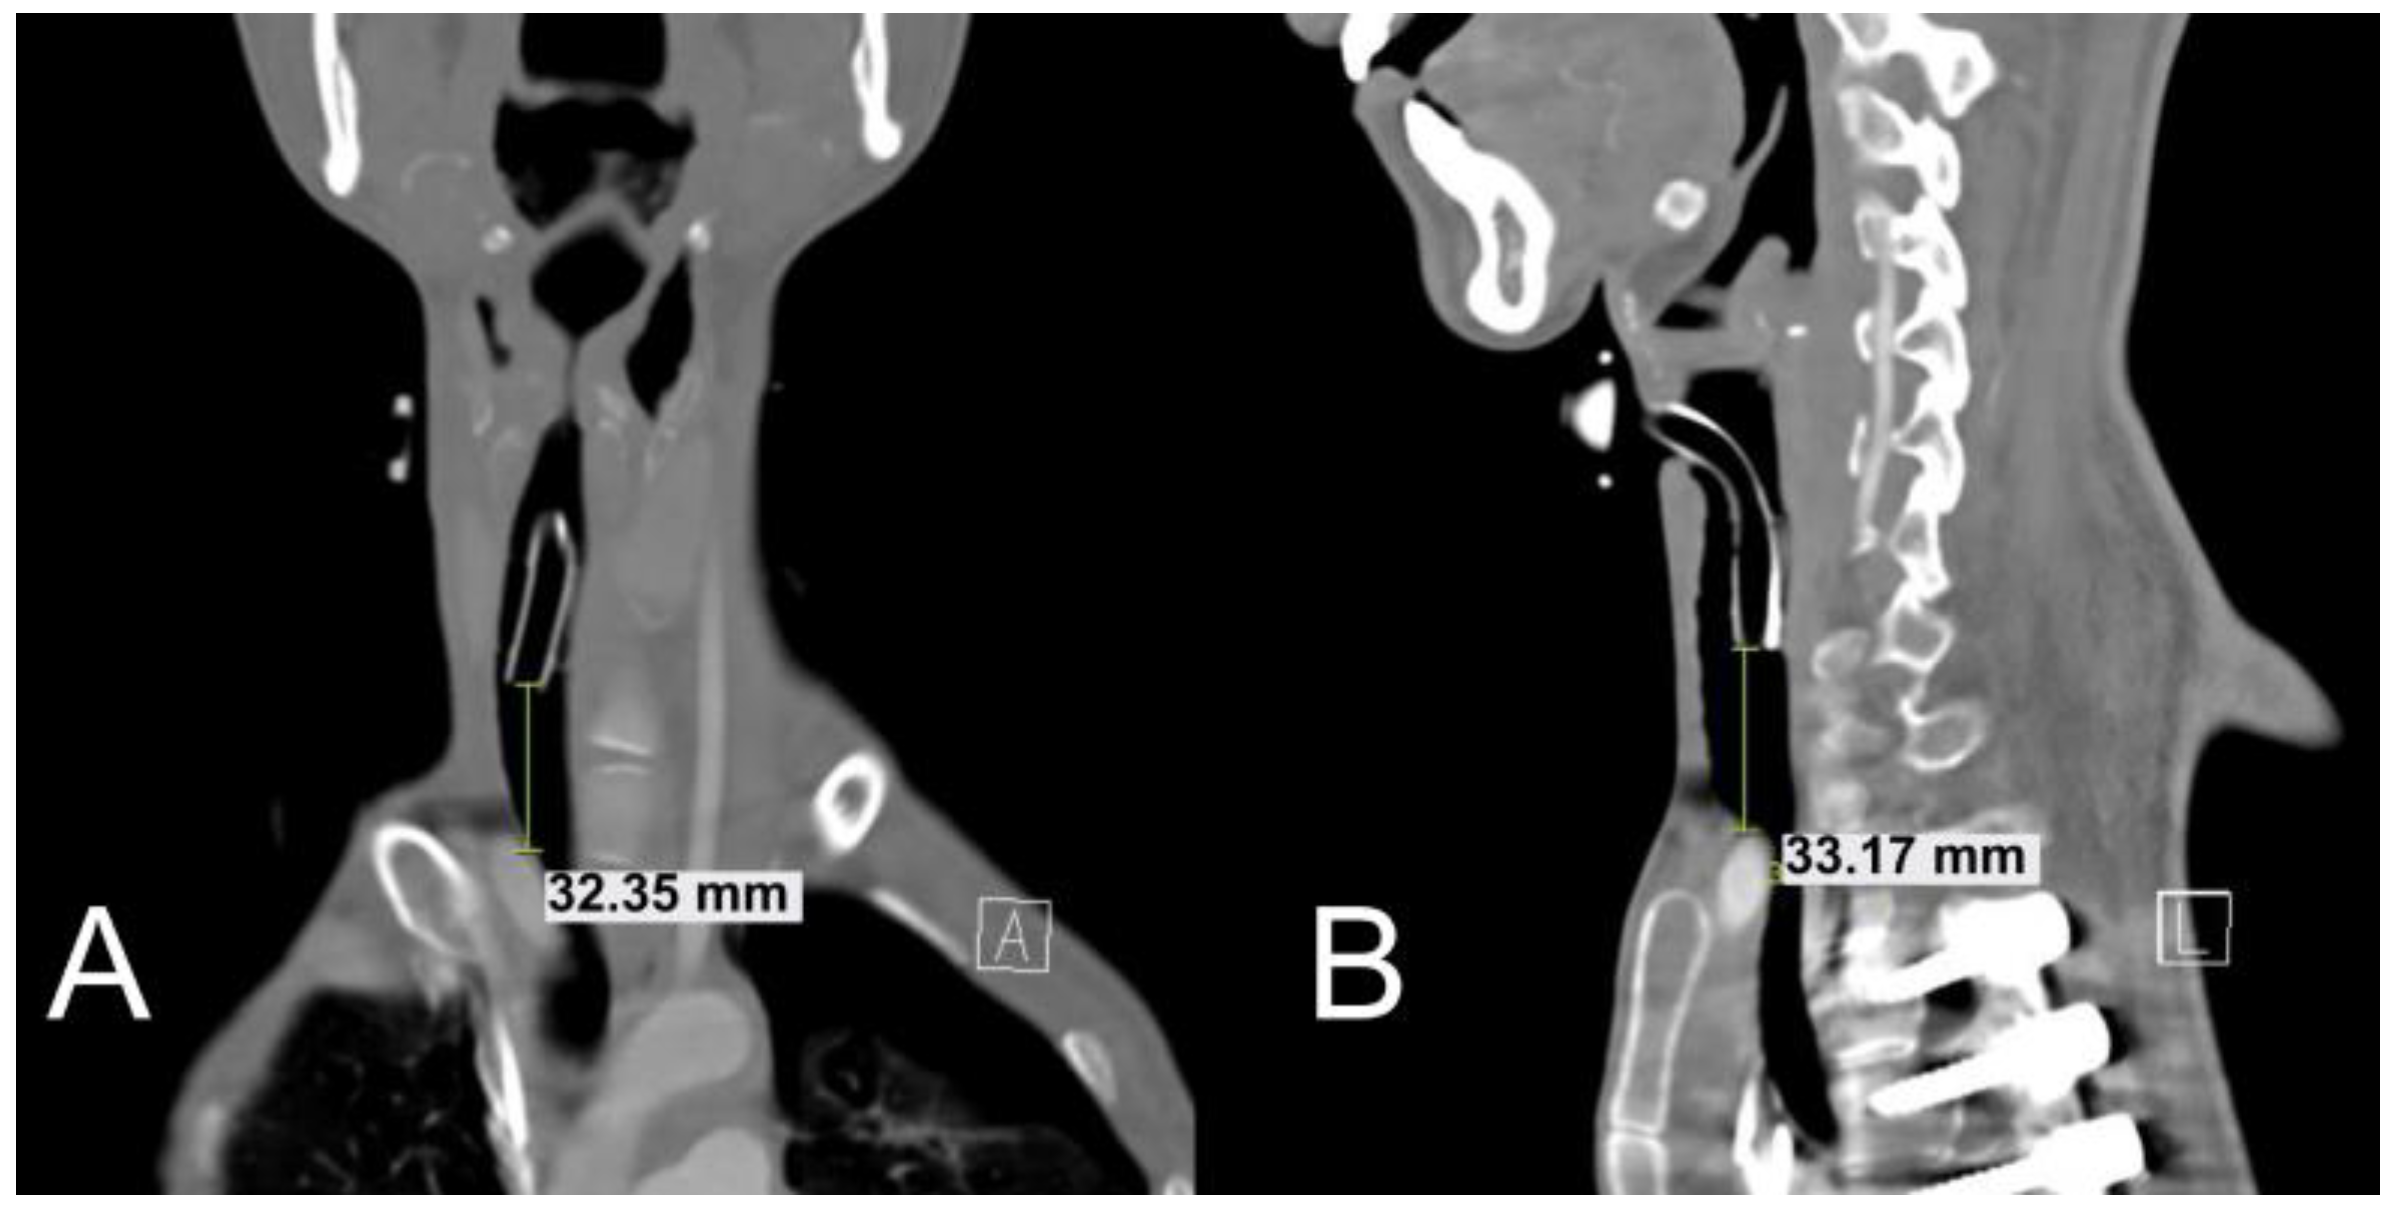

2.1. Case 1

2.2. Case 2